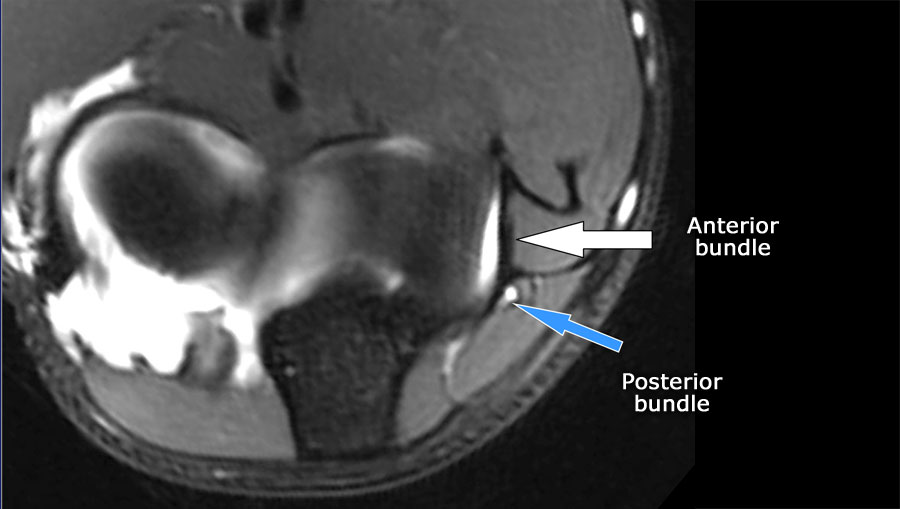

Luôn sử dụng hình ảnh mặt cắt ngang (axial) khi nghiên cứu các dây chằng, đặc biệt là dây chằng bên trụ (UCL).

Scroll through the images.

- Nếu bạn nhìn vào mỏm trên lồi cầu trong, bạn sẽ nhận thấy bó sau như một cấu trúc mỏng (mũi tên xanh).

- Notice the ulnar nerve sitting in the cubital tunnel.

- The posterior bundle forms the floor of the cubital tunnel.

- A retinaculum covers the cubital tunnel.

- Lưu ý rằng bó trước dày hơn nhiều (mũi tên trắng).

- Bạn có thể thấy sự khác biệt giữa dây chằng trước và dây chằng sau mặc dù chúng tạo thành một dây chằng duy nhất.

- Khi đi về phía xa, chúng ta sẽ thấy chúng hợp nhất lại để bám vào củ sublime.